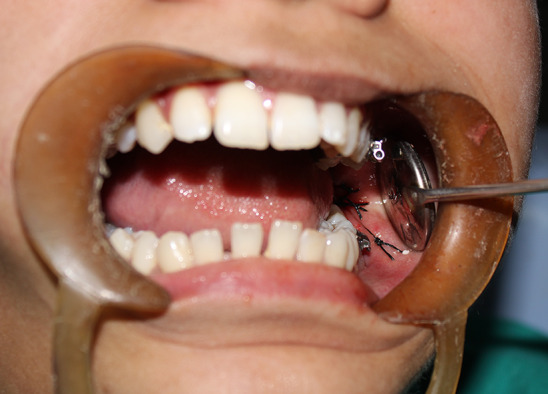

This study was carried out as a randomized controlled clinical trial: split mouth design (Fig. 1). The estimated sample size was calculated by taking the means of mouth opening, facial swelling and wound dehiscence from a previous similar study conducted by Jiminez et al. [11] with a confidence level of 95% and power of 80%. The calculated sample size was 13 patients (26 operating sites). 20% was added to the sample size from the start of the study to compensate for drop-out. Therefore, 16 patients (32 operating sites) who required removal of bilateral impacted lower third molars were recruited from the outpatient department of oral and maxillofacial surgery after fulfilling the inclusion and exclusion criteria. The inclusion criteria were patients with age ranging from 18 to 60 years having bilateral mandibular impacted third molars with no systemic disorders and who have second molar present in the oral cavity. The exclusion criteria were heavy smokers, uncontrolled systemic conditions, pathologies, and infection at the site of surgery, missing second molar tooth and patients not ready to give the written consent. The selected patients were randomized and allocated to one of the groups. Randomization was done by envelope method; 16 sets of unmarked envelopes were prepared. Each set contained two envelopes, one having a paper slip with ‘Study’ written on it and the other having ‘Control’ written on it. The side to be operated first was decided after discussion with the patient. The nurse opened one of the envelopes and conveyed whether the side would be study side or control side. All operations were performed by qualified maxillofacial surgeon under local anesthesia consisting of 2% lidocaine hydrochloride with 1:80,000 (Lignox, Warrant Pharmaceutical, India). A modified Ward's incision was used in all the cases. The impacted tooth was removed by standard technique. The flap was repositioned and sutured with 4–0 silk suture (Truesilk, Suture India, India). Both the groups received the same postoperative prescription except the antibiotic. In group A (control group), the patients were given Tab. Amoxicillin 500 mg with clavulanic acid 125 mg (Tab. Klavimed 625 mg, Indomed, India), thrice daily for 3 days. Group B (Study Group) patients received Antibiotic Impregnated Microbeads (AIM), containing amoxicillin 500 mg and clavulanic acid 100 mg placed in situ (Fig. 2) in the extraction socket before primary closure (Fig. 3).

Antibiotic Impregnated Microbeads (AIM) placed in the extraction socket

Wound closure after AIM placement